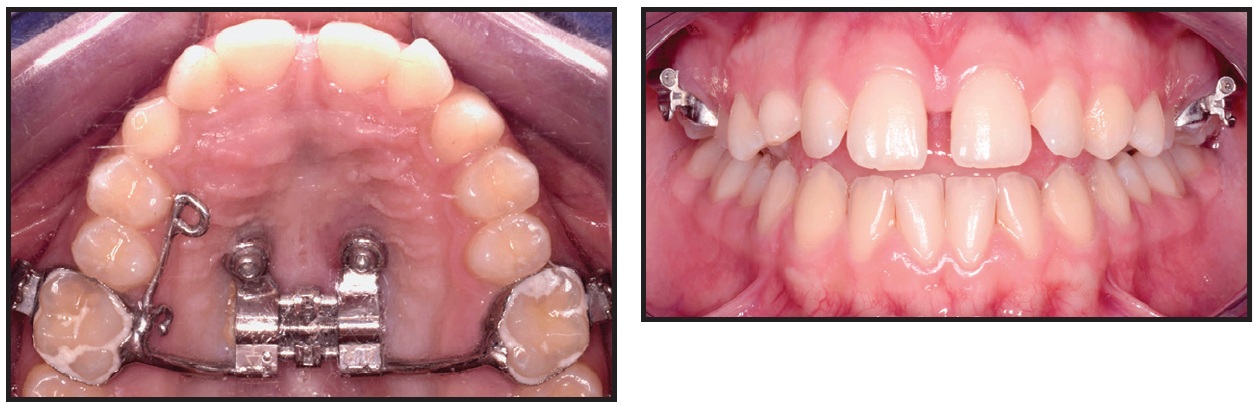

After local anesthesia (2% lidocaine) was administered in the surgical sites, the surgical guide was fitted to the occlusal surfaces of the posterior teeth. Two OrthoEasy Pal** miniscrews were inserted into the adapted pickup driver and mounted on a contra-angle handpiece at a low speed of 40rpm (Fig. 8). The cylindrical guide tubes were designed according to the dimensions of the pickup driver to ensure that the screws were inserted at the correct angle and the planned depth (Fig. 9).

Fig. 9 Two parallel miniscrews after insertion in anterior palate.